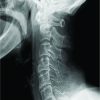

We are presenting 35-years-old free medically, active soldier referred to the orthopedic clinic from family medicine after noticing abnormal incidental findings on X-rays (Fig. 1-4).

He has good quadriceps and hamstring power 5/5. No other abnormalities were detected in his upper and lower limbs. Potential biomechanical adaptations that help to maintain normal gait and joint kinematics in this patient with congenital absence of the patella, specifically mechanisms that prevent knee hyperextension. This may include strengthening or altered recruitment of surrounding musculature (e.g., hamstrings, hip flexors, gastrocnemius), and modified joint alignment or ligament tensioning within normal compare to other studies. Both static postures and dynamic loading scenarios, for example, walking and stair climbing, have been stable movements, which are normally enhance quadriceps efficiency by increasing the moment arm and increased hamstring stress due to compensatory function in absence of the patella (Fig. 5). His blood parameters of liver function test, renal function test, and bone profile and labs are all normal (Table 1). Patient’s hip joints demonstrated a normal range of movement and his ankle joints were also normal. The rest of her musculoskeletal exam was also normal. His cardiovascular, neurological, and abdominal examinations were all normal (Fig. 5). CT chest, abdomen, and pelvis showed no osseous or visceral abnormal. (Fig. 7 & 8).